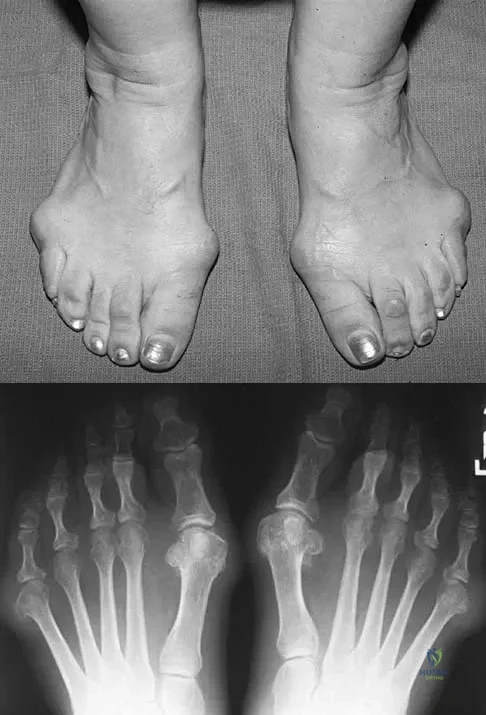

Question 40

Figures 5a and 5b show the clinical photograph and radiograph of a patient who has difficulty wearing shoes and has persistent symptoms medially and laterally at the first and fifth metatarsophalangeal joints. Because shoe modifications have failed to provide relief, management should now consist of

Explanation